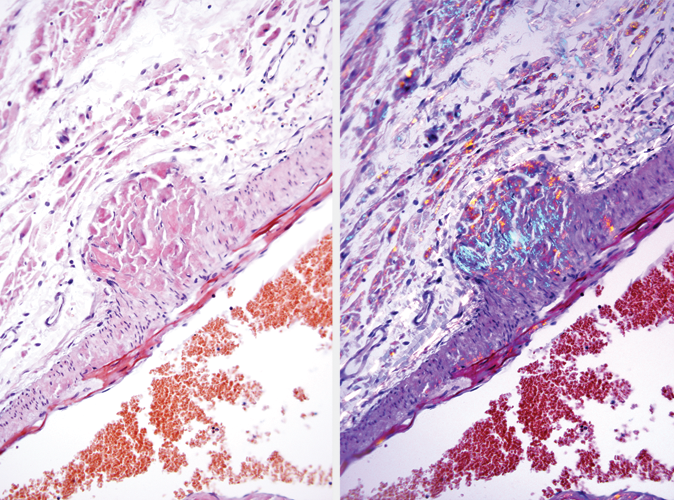

The Congo Red, Amyloid Stain Kit